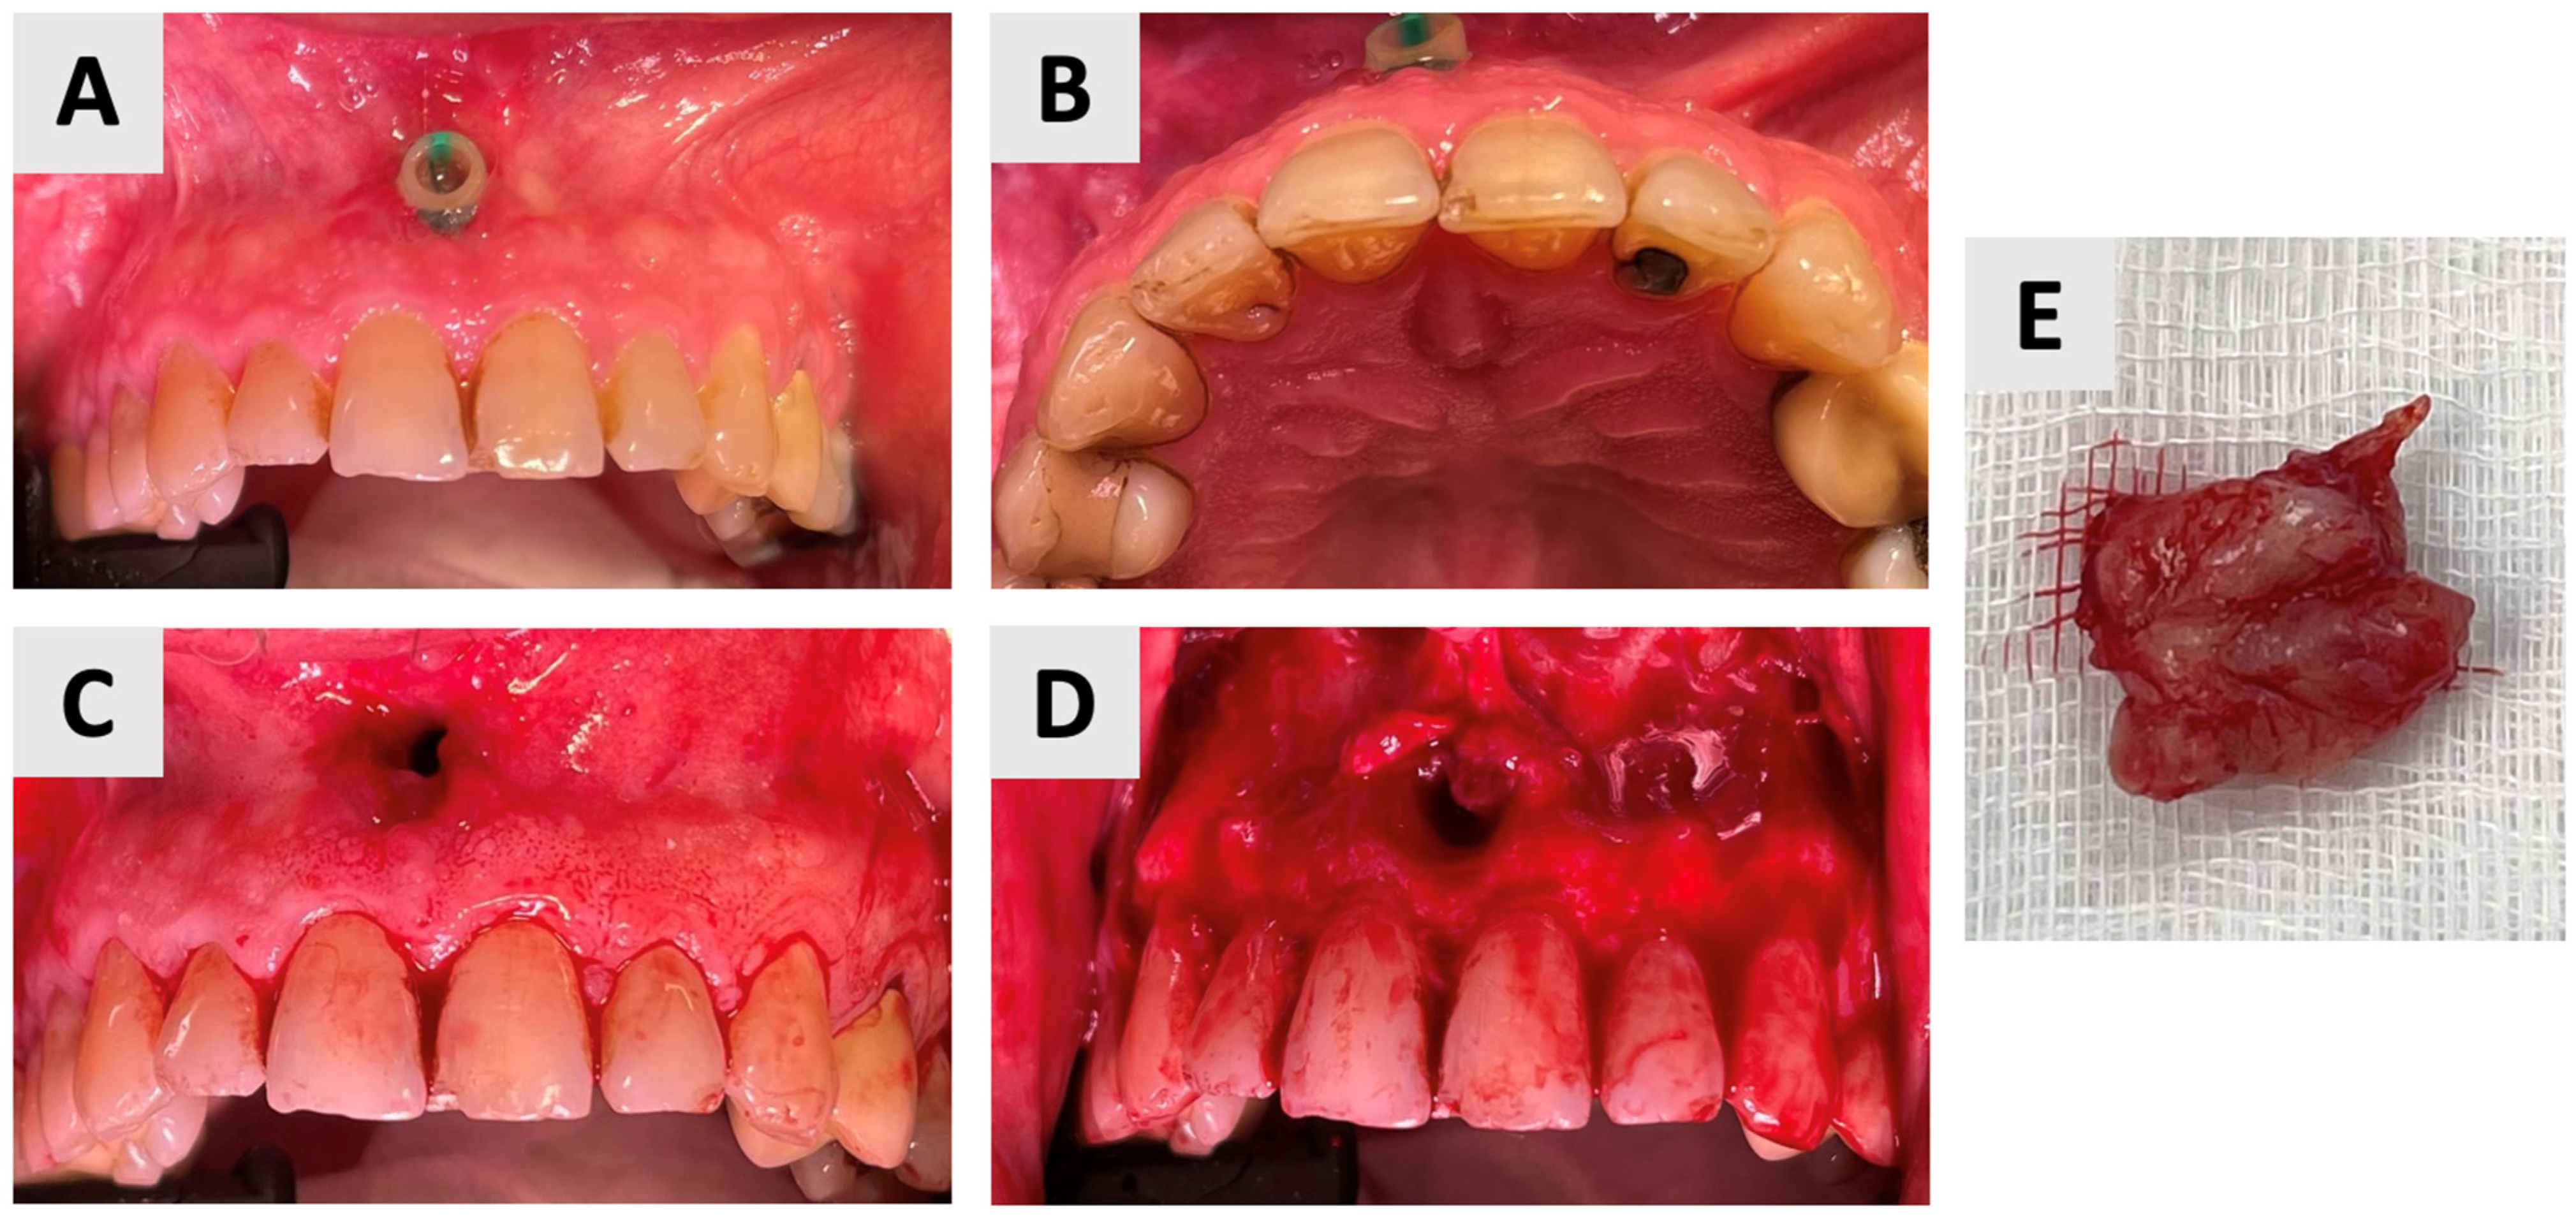

Given the size of the resulting osseous defect, it was important to ensure stabilization with a bone graft to prevent the collapse of surrounding vital structures and to promote optimal bone regeneration. An additional challenge was the fact that the cyst had extensively eroded and destroyed part of the palatal bone wall, leaving only a thin layer of palatal soft tissue separating the oral cavity from the underlying bony defect. This anatomical deficiency was a limitation, as it is well known that successful graft compaction and stabilization require a firm structural base. To address this issue, a resorbable magnesium metal membrane (NOVAMag®, botiss GmbH, Zossen, Germany) was carefully positioned within the defect to serve as a biomechanical scaffold, effectively reconstructing the firm base of the cavity (Figure 4B). Following the placement of the magnesium membrane to reconstruct the defect base, the cavity was filled with anorganic bovine bone xenograft (cerabone®, botiss GmbH, Zossen, Germany). A second magnesium membrane was then carefully positioned over the filled defect, serving as a barrier to prevent soft tissue ingrowth and to GBR (Figure 4E). Then, to improve soft tissue healing at the site where the marsupialization drain had been placed, a platelet-rich fibrin (PRF) membrane was prepared and applied (Figure 4F). Root canal treatment was performed during this phase based on the absence of clinical symptoms and signs of infection during the marsupialization phase. Therefore, following the completion of the bone grafting procedure, immediate root canal treatment was performed using gutta-percha and an epoxy resin-based sealer (AH Plus®, Dentsply Sirona, Bensheim, Germany) for the root canal obturation. A retroalveolar post-procedure radiograph obtained immediately after the augmentation and endodontic procedures revealed satisfactory bone graft condensation within the defect and adequate endodontic filling of the treated teeth (Figure 4H).

Figure 4.

Augmentation of cystic defect: (A) Following soft tissue retraction (full mucoperiosteal flap from canine to canine with vertical incisions beginning at the distal transitional line angle of the maxillary canines extending beyond the esthetic zone) to expose the osseous defect, a resorbable magnesium membrane was prepared for placement within the defect cavity. (B) The magnesium membrane is carefully positioned at the base of the defect, acting as a structural support to bridge the bony discontinuity in the palatal bone. (C) The defect is then filled and compacted with bovine bone graft granules. (D) A secondary magnesium membrane is placed over the entrance of the defect, serving as a barrier to secure the graft material and prevent its displacement. (E) The soft tissue flap is repositioned and adapted over the defect site to ensure primary closure. (F) A platelet-rich fibrin (PRF) membrane is prepared and placed over the soft tissue defect to promote wound healing and soft tissue regeneration. (G) Final flap adaptation and primary closure achieved using 3-0 resorbable polyglactin sutures (VICRYL® RAPIDE, Ethicon, Johnson & Johnson Medical Technologies, Cincinnati, OH, USA). (H) Intraoperative retroalveolar radiograph focusing on the apical region of the maxillary incisors, demonstrating satisfactory bone graft condensation within the defect and the working length preparation of the root canals. The post-operative medication regimen followed the same protocol as described after the marsupialization procedure, including antibiotic prophylaxis, analgesic medication, and chlorhexidine oral rinses. A structured follow-up protocol was established, comprising weekly visits for the initial four weeks, followed by a comprehensive assessment at six weeks post-surgery.